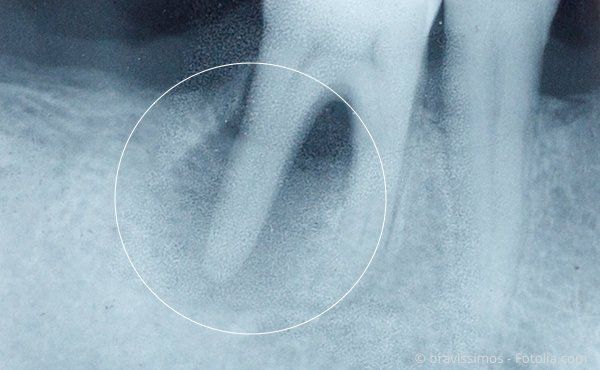

Wurzelbehandlung: Entzündung an der Wurzel eines abgestorbenen Zahnes im Röntgenbild

Zahnfilme / Aufnahmen im Mundinneren: Diese speziellen Röntgenbilder werden direkt in Ihrem Mund aufgenommen. Sie sind sehr detailgetreu und bilden rund zwei bis vier Zähne ab. Damit lässt sich auch der „Röntgenstatus“ ermitteln, indem die einzelnen Zahnfilme Ihres gesamten Gebisses nebeneinander gelegt und miteinander verglichen werden.

Mit einem sog. Orthopantomographen (OPG) kann eine Panoramaaufnahme erstellt werden, die beide Zahnreihen vollständig auf einem Foto abbilden kann. Zusätzlich zeigt sie den Kiefer und damit den Zustand des Kieferknochens auf. Die Aufnahmen unterstützen die Behandlung, da sie die Wurzelkanäle deutlich zeigen und wir die einzelnen Behandlungsschritte überprüfen können.